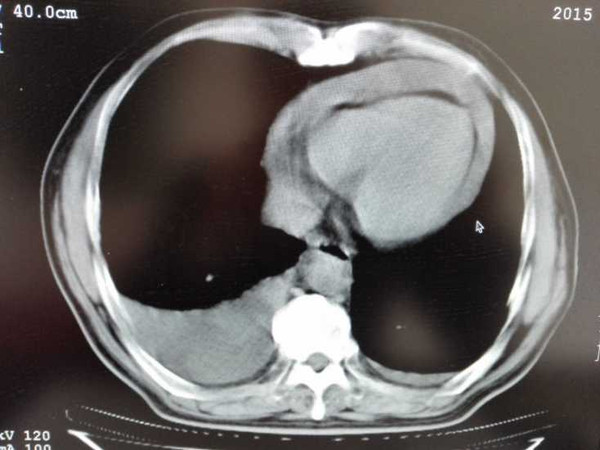

一旦病情逐渐加重,就会出现水肿蔓延全身的症状,还会引发腹水、胸腔积液、纵隔积液、心包积液、肺水肿的现象。

全身性的水肿,患者一定要及时治疗,因为一旦胸腔积液在0.5L以上后,人就会感觉到呼吸不适,影响正常生活。

长时间心包积液会发展为慢性心包积液,量大时有可能导致心包填塞,甚至导致死亡。